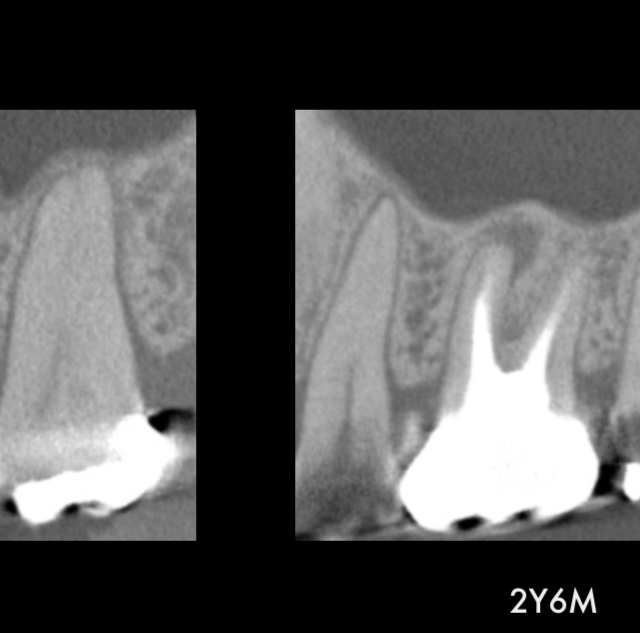

ダウンタイムの少ないインプラント